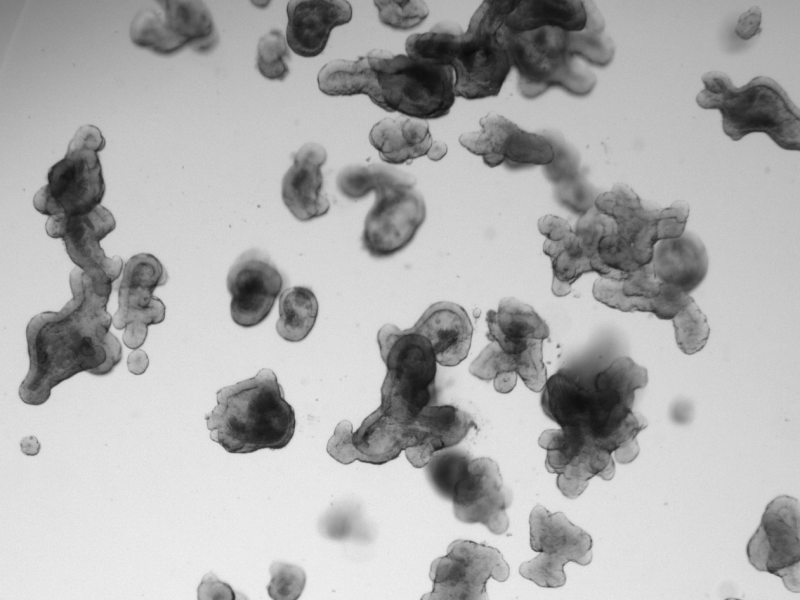

Antibodies with a mission: what the Utrecht Monoclonal Antibody Facility (UMab) can do for you 27 Jul 2021